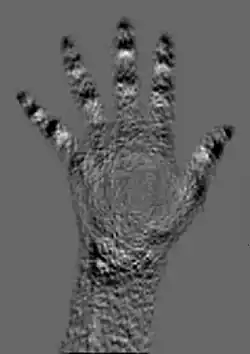

A typical image is shown in Figure 3.10. It can be seen that bone has a brighter shade of grey than that of the enveloping tissue and is brighter still than the surrounding air. This is the conventional method of displaying a radiograph such that higher photon attenuation is encoded as a brighter shade of grey.

From our earlier discussion, we can expect bone to absorb X-rays preferentially relative to the surrounding tissue and that the energy of these X-rays should have a strong influence on this absorption difference. It is this difference which generates contrast in radiographic images, and we can therefore expect contrast to reduce with increasing X-ray energy. We can also expect that the influence of scatter should be apparent at all X-rays energies.

It might be thought that such absorption differences could be used in determining, for instance, the physical density of bone, or indeed the density of tissue. However the presence of scattered radiation has a strong, detrimental effect on such densitometric measurements, as we will see later.